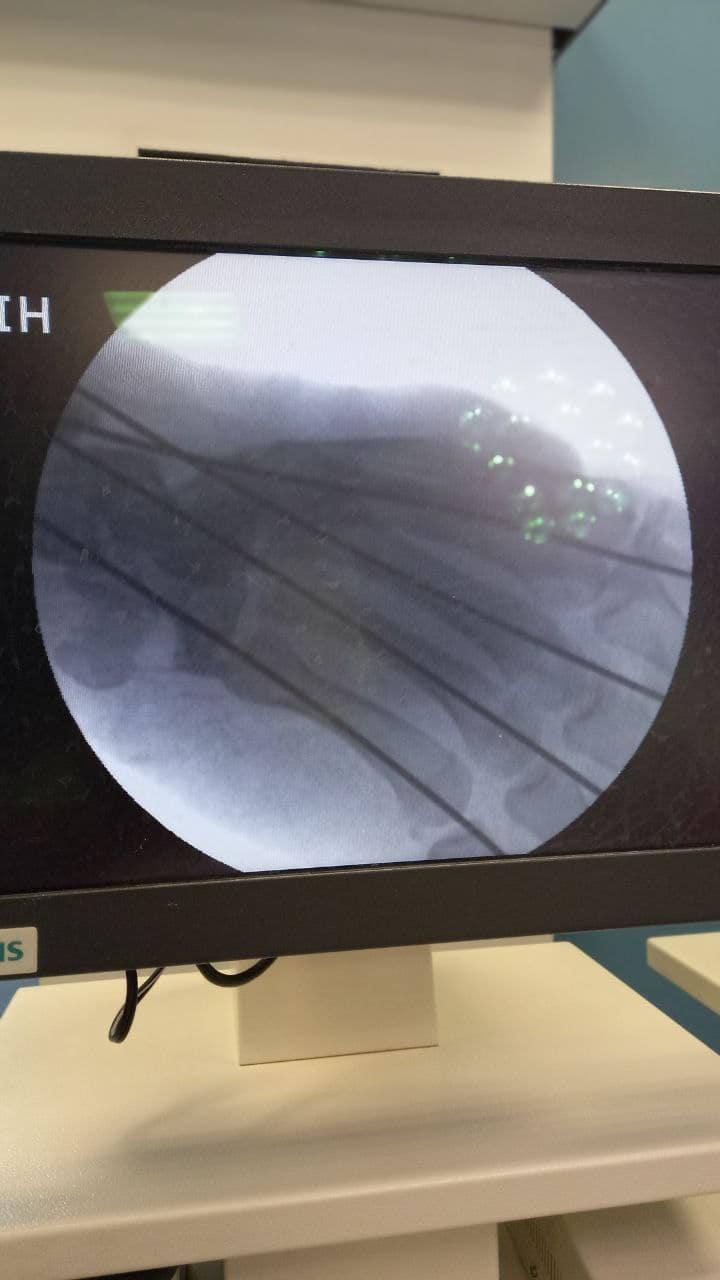

Також зазначається, що пацієнту провели фасціотомію: розрізали сполучну тканину, щоб зняти тиск в кінцівці, і зібрали всі кісточки кисті разом.

Зазначається, що кістки пальців травматологи зафіксували чотирма спицями Кіршнера, які пацієнт носить вже близько місяця.